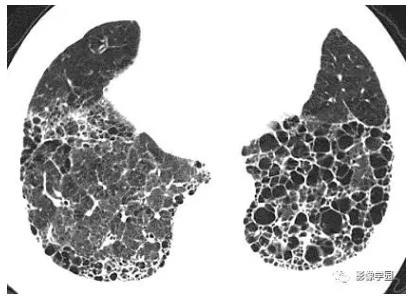

间质性肺炎蜂窝肺图片,间质性肺炎图片

hrct影像:纤维化和蜂窝样变之特发性肺纤维化 (ipf)

蜂窝肺的定义与探讨

蜂窝肺图片

肺纤维化蜂窝肺